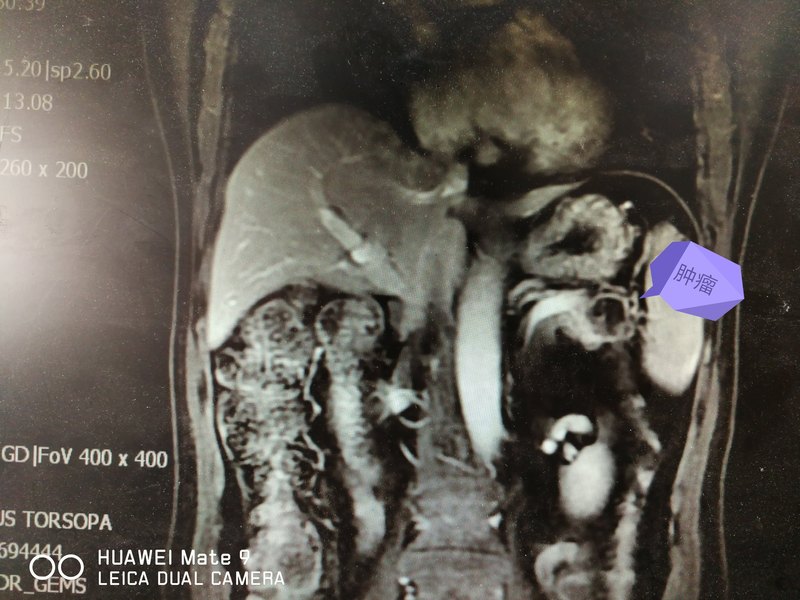

腹腔鏡胰體尾切除術(shù)是目前報道最多、最為普及、最為成熟的一類腹腔鏡胰腺手術(shù)??梢苑譃楸F⒑吐?lián)合脾臟切除兩類術(shù)式。通常觀點(diǎn):胰腺惡性腫瘤,為達(dá)到手術(shù)根治效果,往往聯(lián)合脾臟切除;胰腺良性腫瘤,如果可以保留脾動靜脈或僅保留胃短血管脾臟沒有梗死,可以保留脾臟。 我院(青島市市立醫(yī)院本部肝膽外科)已經(jīng)開展腹腔鏡下胰體尾腫瘤切除手術(shù)多年,具有豐富的臨床經(jīng)驗,下面我們就科普下胰體尾腫瘤腹腔鏡下切除的適應(yīng)癥和禁忌癥: 1 腹腔鏡胰體尾切除術(shù)適應(yīng)證: 1)胰體尾部各種良性腫瘤,如胰腺內(nèi)分泌腫瘤、漿液性囊腺瘤等; 2)胰體尾部各種交界性腫瘤,如交界性黏液性囊腺瘤、導(dǎo)管內(nèi)乳頭狀瘤等; 3)胰體尾部各種惡性腫瘤,且術(shù)前評估與周圍組織粘連較輕無遠(yuǎn)處轉(zhuǎn)移者,如胰腺癌等; 4)胰腺損傷、慢性胰腺炎; 5) 胰腺炎合并假性囊腫。 2.腹腔鏡胰體尾切除術(shù)的禁忌證主要有: 1)胰腺惡性腫瘤,考慮與周圍組織粘連較重分離困難,術(shù)中可能損傷周圍臟器或重要血管; 2) 急性胰腺炎發(fā)作期; 3) 術(shù)前考慮腹腔主要血管侵犯或惡性腫瘤鄰近器官轉(zhuǎn)移; 4)既往上腹部手術(shù)史; 5)心肺等重要臟器功能障礙,不能耐受手術(shù)治療。 近年來,腹腔鏡胰體尾切除術(shù)逐步推廣,大宗病例報道及與開腹胰體尾切除手術(shù)對照研究均顯示:手術(shù)時間、出血量、死亡率、住院時間的方面腹腔鏡手術(shù)均優(yōu)于開腹手術(shù),而并發(fā)癥發(fā)生率如胰漏、出血等與開腹手術(shù)相似。